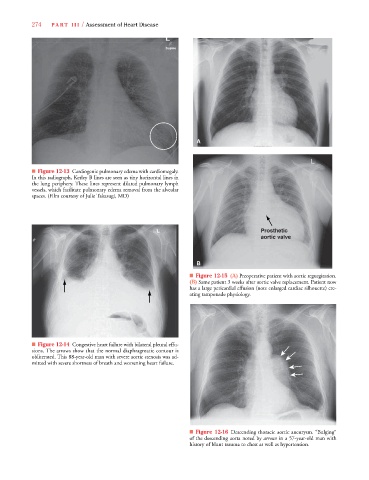

■ Figure 12-13 Cardiogenic pulmonary edema with cardiomegaly.

In this radiograph, Kerley B lines are seen as tiny horizontal lines in

the lung periphery. These lines represent dilated pulmonary lymph

vessels, which facilitate pulmonary edema removal from the alveolar

spaces. (Film courtesy of Julie Takasugi, MD)

■ Figure 12-15 (A) Preoperative patient with aortic regurgitation.

(B) Same patient 3 weeks after aortic valve replacement. Patient now

has a large pericardial effusion (note enlarged cardiac silhouette) cre-

ating tamponade physiology.

■ Figure 12-14 Congestive heart failure with bilateral pleural effu-

sions. The arrows show that the normal diaphragmatic contour is

obliterated. This 88-year-old man with severe aortic stenosis was ad-

mitted with severe shortness of breath and worsening heart failure.

■ Figure 12-16 Descending thoracic aortic aneurysm. “Bulging”

of the descending aorta noted by arrows in a 57-year-old man with

history of blunt trauma to chest as well as hypertension.